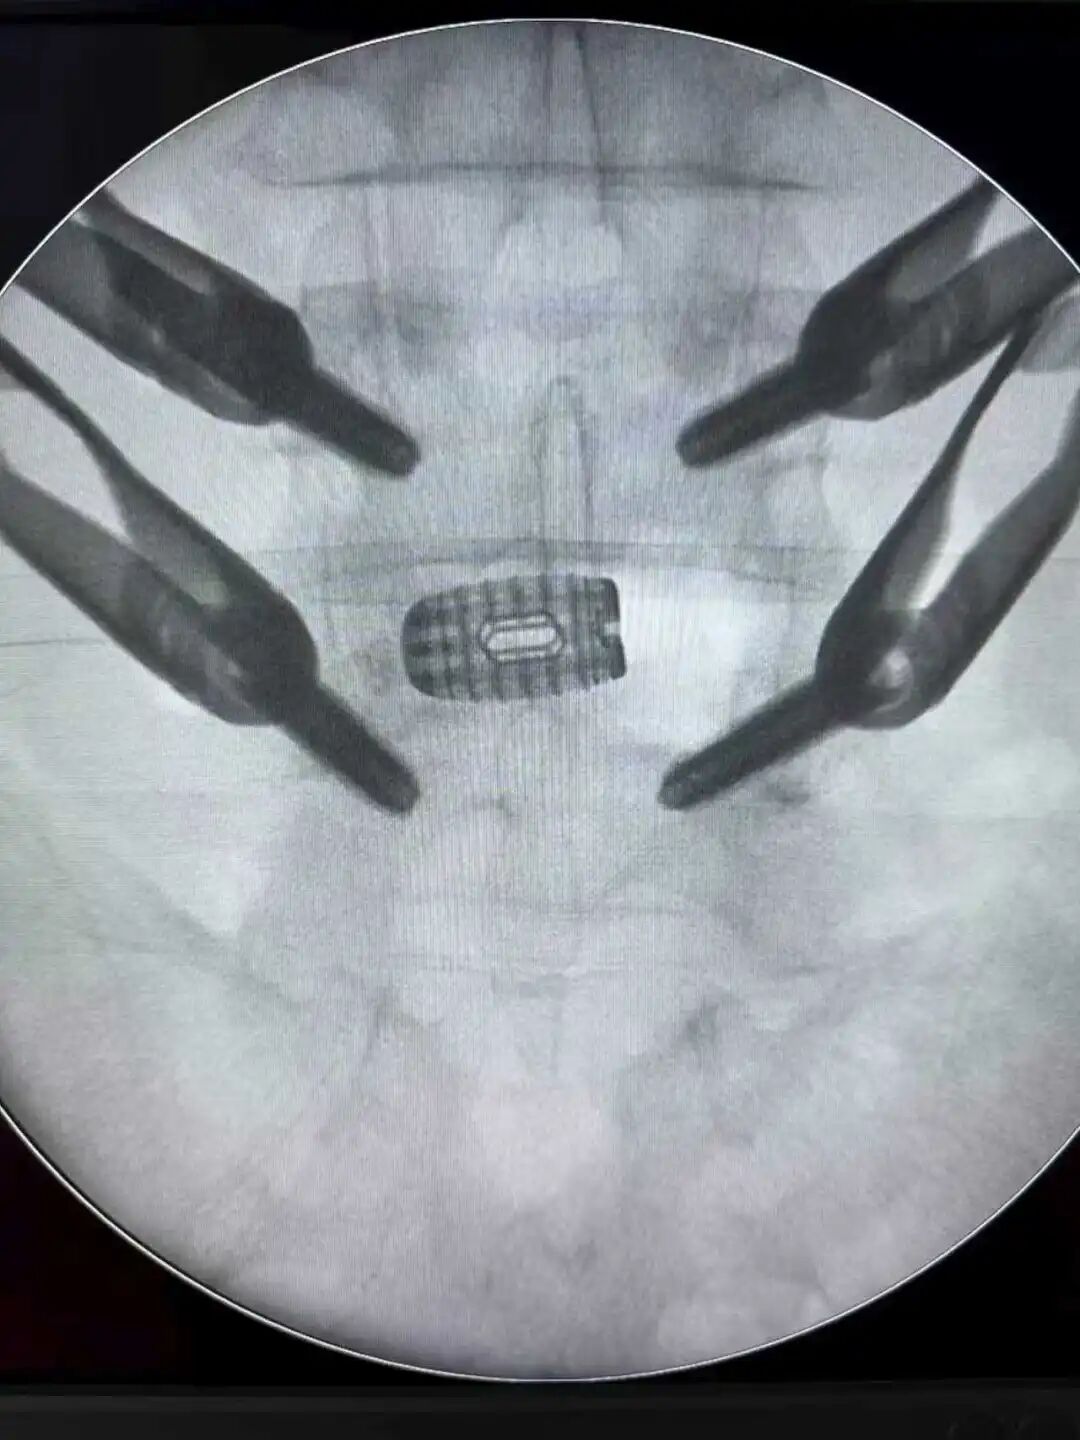

针对黄先生的病情,脊柱外科团队进行了反复讨论和评估,最终决定为他采用“”数字+组合微创”技术,即Auss技术3D 打印Cage镜下融合术。

手术首先采用经皮椎弓根螺钉固定技术,通过几个微小切口植入椎弓根螺钉,为脊柱提供稳定支撑。医生在高清影像设备引导下精准操作,每个步骤都准确无误。

最后,植入3D打印椎间融合器完成融合。这种融合器根据患者解剖结构个性化定制,表面特殊纹理能更好地与骨组织结合,大大提高了融合成功率。